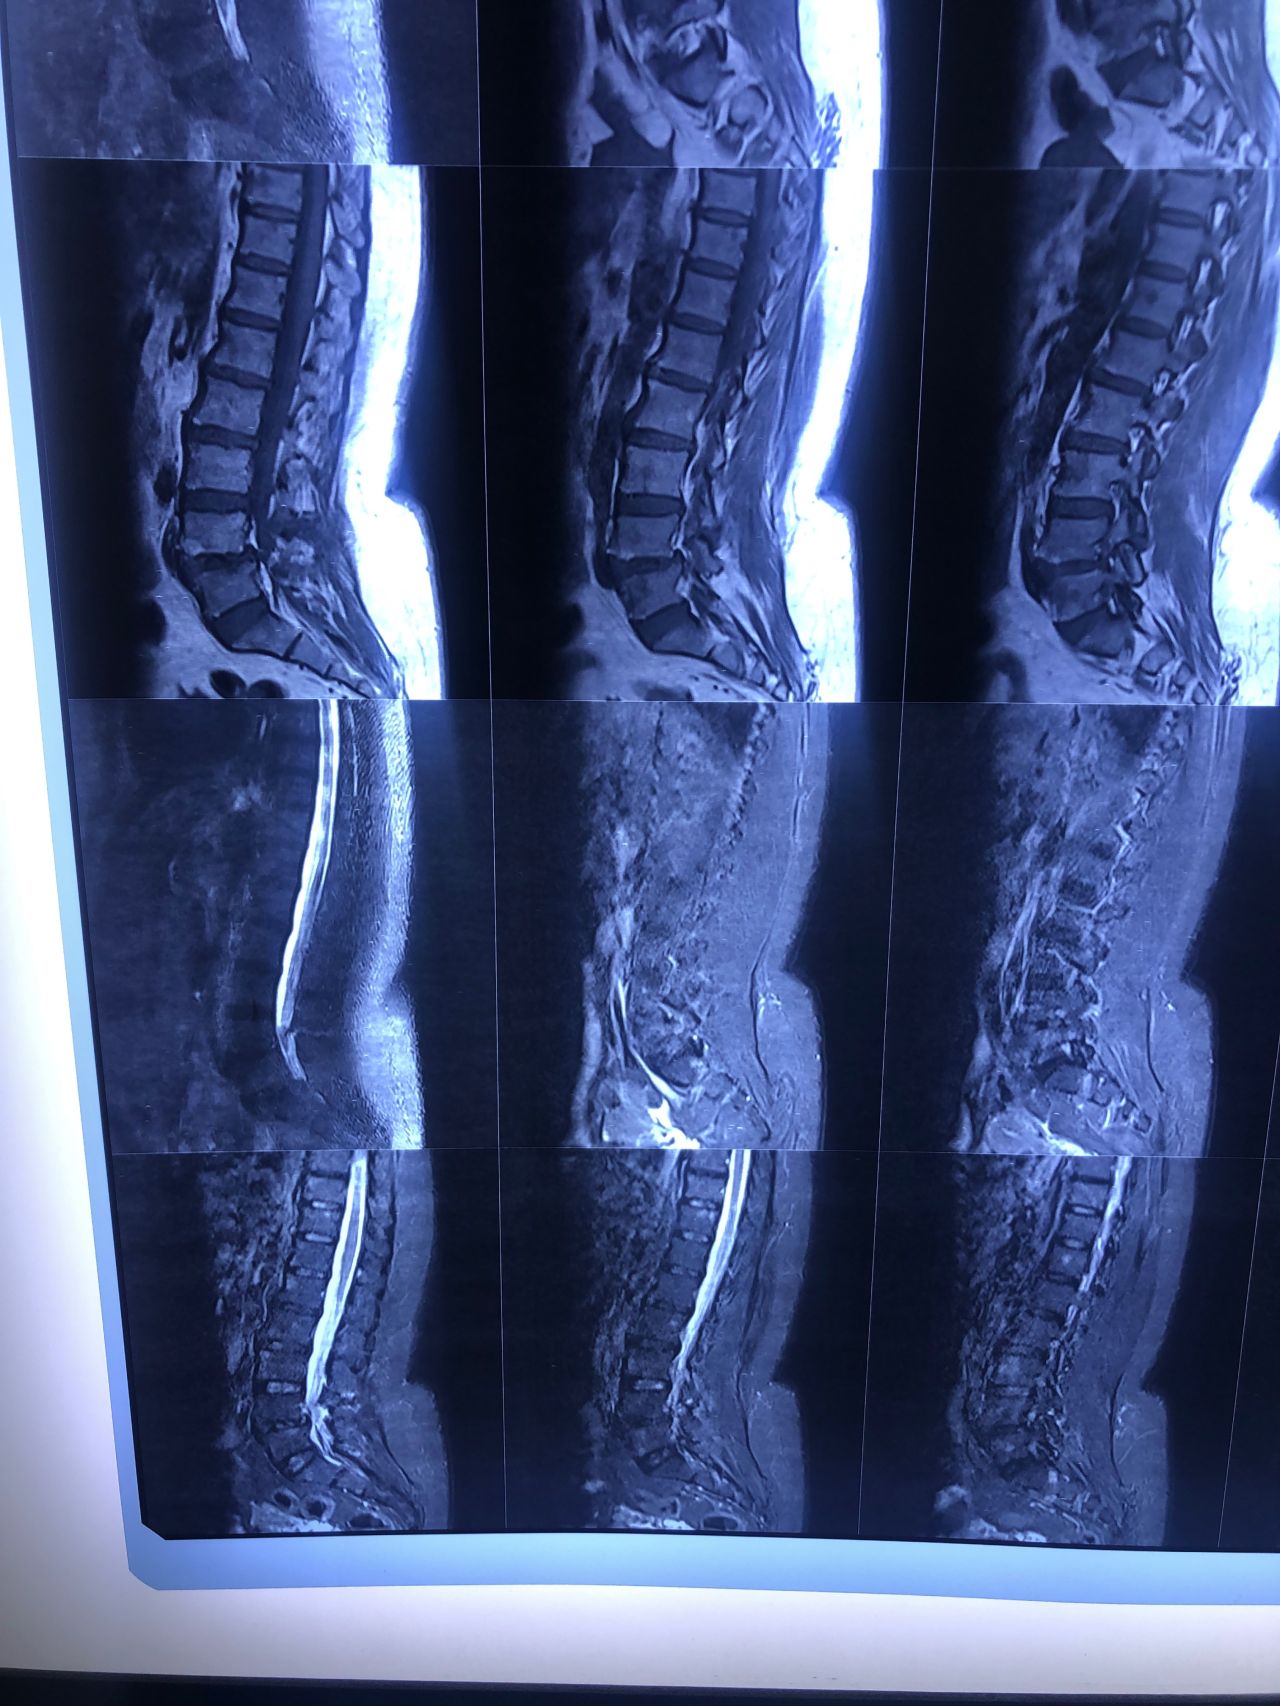

L4-L5 level:

sever L4-5 canal stenosis mainly due to FL hypertrophy?

CSF block. Mild L3 retrolisthesis, facets hypertrophy bilateraly causing L and R IVF stenosis, disc hyperbule

Since I’ve noticed instability in some segments I asked for dynamic L/S x ray:we see mild L4 ant listens due to DjD/DDD. There is not any pars defect.

In cervical mri I marked some findings plus their reports

I will give her treatment via Cox chiropractic flex dis and axial decompression. I would use DTS decompression

Since there is a few mild to moderate DjDs/ DDs in her lower back I won’t use lumbar adjustment on her